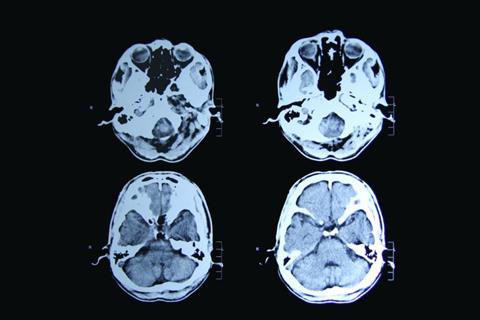

The gene therapy contains a genetically altered virus containing DNA which when administered into the striatum (caudate and putamen) in the brain, results in lower levels of the mutated huntingtin protein, which would otherwise kill neurons.